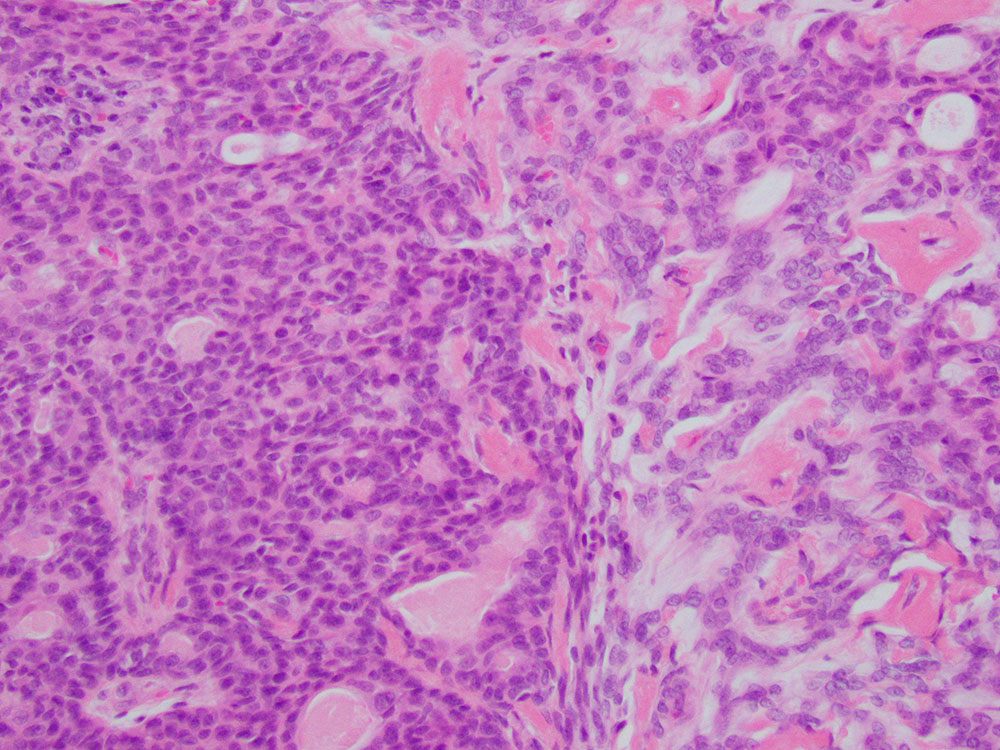

Sonographically, the lesion was located in the deep dermis and subcutaneous fat and appeared solid. Biopsy of the lesion was performed by a dermatologist. Histologic sections revealed a tumor with tubular and ductal structures lined by basaloid epithelial cells. Focally there was myxoid stroma present (Figures 1 and 2). Immunohistochemically, the neoplastic cells were positive for CAM 5.2 (Figure 3), p63, p40 (Figure 4), S-100 (Figure 5), and GFAP (focal, Figure 6), but negative for smooth muscle actin (SMA) (Figure 7). Rearrangement of the PLAG1 (8q12.1) locus was present in 96% of interphase cells by fluorescence in situ hybridization, supporting the diagnosis.